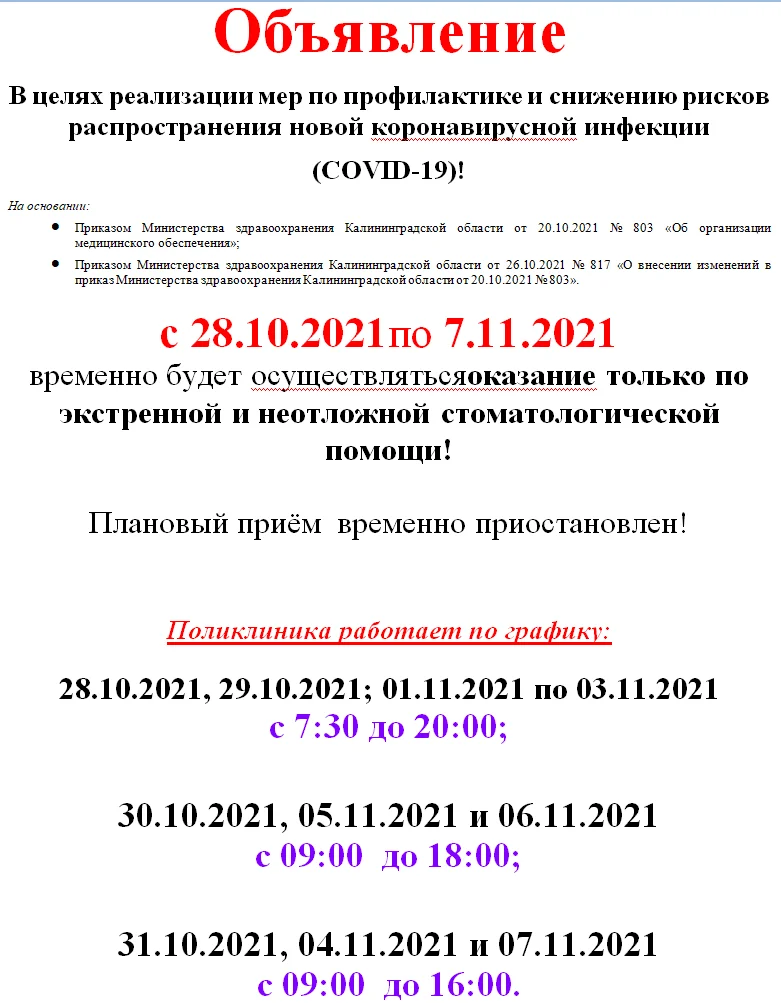

29.10.2021